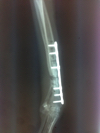

昔はピンを入れたり、DCP等のプレートを挿入して治療していましたが、最近はチタン製のロッキングプレートを用いての治療が主流です。

同じように見えるプレートとネジでも以前の方式(DCP等)ではプレートを骨の形状に合わせてなるべくぴったりするように固定しなければなりませんでした。

これら旧タイプのプレートでは骨折の治癒には最も重要な骨膜を阻害してしまうデメリットがあります。もちろんこれでも治癒しますが中には難し症例もあります。

現在動物で使用できるロッキングプレートにも数種類あり、当院ではLCP、SOP、PAX、titanlockの4種類を使い分けています。

こちらの症例は2度目の骨折です。それも2回目の骨折でプレートがうまくはまっていなかったので今回ロッキングプレートにてやり直しました。

これまた小型犬の橈尺骨の骨折です。関節に近い場所なので固定が難しいです。